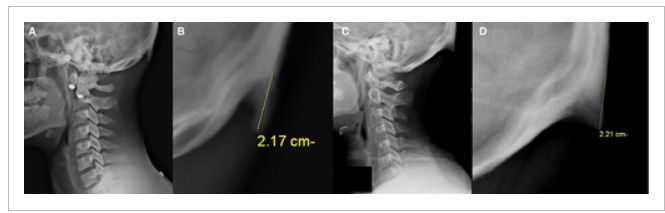

然而,随着电子设备的普及,越来越多的年轻人中发现了这种异常的骨质突出物。Shahar的这项研究最早发表在2016年的《解剖学杂志》(Journal of Anatomy)上,查看了218名18岁-30岁的年轻患者的X光片,并设定了一个5mm的阈值来记录枕外隆突的情况——一般的骨刺在3到5mm就算很大了,如果“隆突”长度超过10mm,则认为是枕外隆突过大。他们发现41%参与者的头骨有出现枕外隆突过大的情况。

(A,B):A组参与者的X光片;(C,D)B组参与者的X光片;(B,D)分别在A,C中扩大了周围区域的图像,包括扩大的枕外隆突;(B,D)图像中的测量线,指示了扩大的枕外隆突的起点、尖端和长度

他们还发现男性枕外隆突的现象(67.4%)显著高于女性(20.3%),男性平均枕外隆突的大小(15±7 mm)也显著大于女性(10±4 mm)(P < 0.001)。男性参与者中最长的枕外隆突为35.7 mm,女性群体中最长的枕外隆突为25.5 mm。